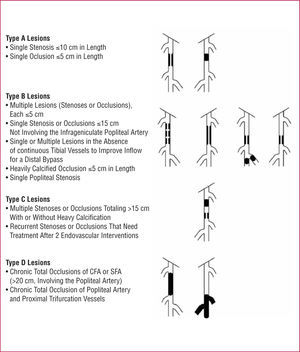

The development of new endovascular techniques has resulted in debate about their role in occlusive arterial disease. An expert group has drawn up a document dealing with the recommendations for treatment, known as the TASC (Inter-Society Consensus for the Management of Peripheral Arterial Disease), whose first edition was published in 2000 and with a second revision announced in 2007.4 This document includes multiple recommendations about the treatment of patients with PAD and establishes 4 categories (A, B, C, and D), according to the morphology and extension of the disease (Figures 3 and 4). Although a detailed analysis of the recommendations is outside the scope of this review, we can summarize by saying that endovascular surgery is recommended for simpler lesions (category A) and open surgery for the more advanced lesions (category D). The indication in the other categories depends on the evaluation of the accompanying diseases, patient preferences after being fully informed, and the experience of the surgical team.

Figure 3. Classification of iliac lesions (TASC II). AAA indicates abdominal aorta aneurysm; CFA, common femoral artery; CIA, common iliac artery; EIA, external iliac artery.

Figure 4. Classification of femoropopliteal lesions (TASC II). CFA indicates common femoral artery; SFA, superficial femoral artery.